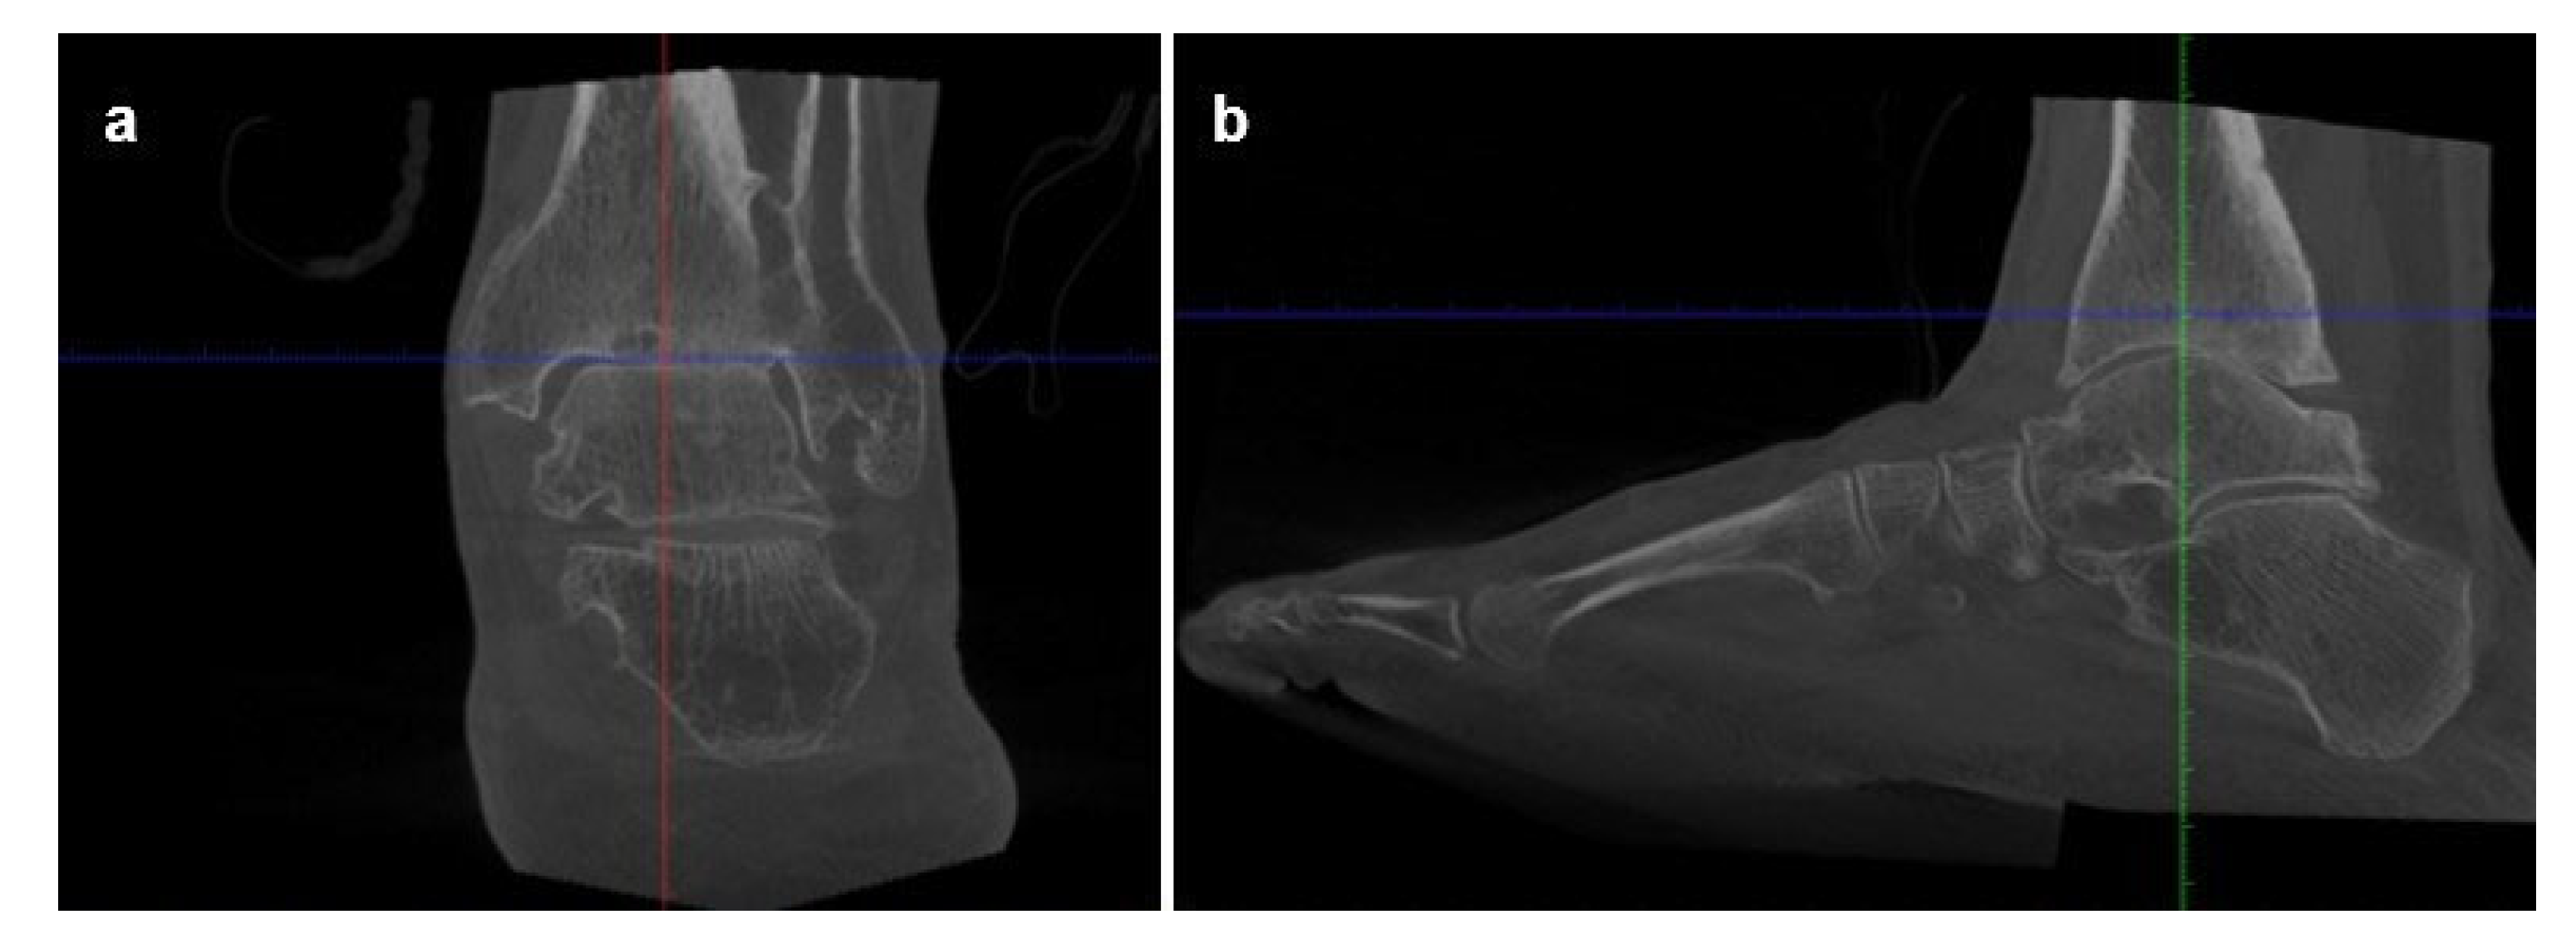

Imaging assessment included conventional bilateral foot and ankle weight-bearing radiographs in anteroposterior, lateral, and Saltzman views (Figure 1), as well as bilateral Weight-Bearing CT (WBCT) scans (Figure 2). Imaging demonstrated advanced right ankle osteoarthritis (Kellgren–Lawrence grade 4[8]) with severe distal tibial bone deformity.

Figure 2. Preoperative weight-bearing computed tomography (WBCT) scans of Case one: (a) Coronal and (b) sagittal WBCT views demonstrating advanced tibiotalar osteoarthritis, distal tibial bone irregularities, and anterior talar shift.